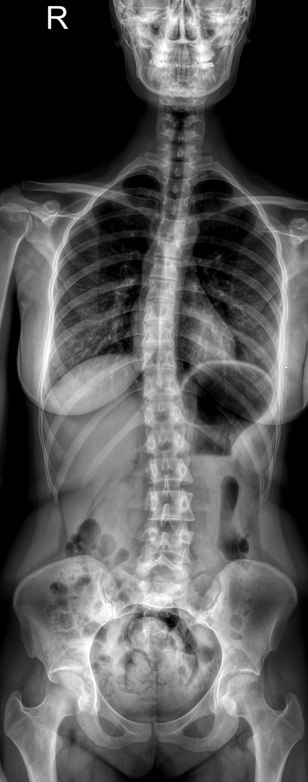

Назад Рентген позвоночника на кифосколиоз в прямой и боковой проекциях

При появлении признаков кифосколиоза или подозрении на него врач в качестве первичного обследования обычно назначает рентген. При этом рекомендован снимок всего позвоночного столба: как для выявления различных аномалий развития позвонков, так и для определения углов отклонения и, соответственно, степени заболевания. Для этого делают несколько обычных прицельных снимков и соединяют их в один с помощью компьютера. Несмотря на большую, казалось бы, дозу облучения, волноваться не стоит. Современное цифровое рентгеновское оборудование излучает настолько маленькую дозу, что даже при серии снимков трудно набрать допустимое для человеческого организма количество облучения.

Врач-рентгенолог  высчитывает углы возникшей деформации. Для определения угла кифоза на боковой рентгенограмме вычерчиваются линии, соединяющие нейтральные, то есть не измененные позвонки, с тем, что находится на самой вершине. Угол между ними и будет искомым. Угол сколиоза определяют по снимку в прямой проекции.

• Угол или углы сколиоза;

• Угол кифоза;

• Изменения шейного и поясничного лордозов: сглаживание или усиление;

• Врожденные аномалии, вызвавшие развитие кифоза;

• Остеопороз, склероз и другие изменения ткани тел позвонков;

• Наличие ротации позвонков;

• Уменьшение межпозвонковых промежутков, признаки дегенеративных процессов в них;

• Переломы, вывихи, новообразования, если они есть.

Для диагностики кифосколиоза необходимы 6 снимков:

• Шейного, грудного и пояснично-крестцового отделов в прямой проекции;

• Те же самые отделы в боковой проекции в состоянии максимального разгибания.